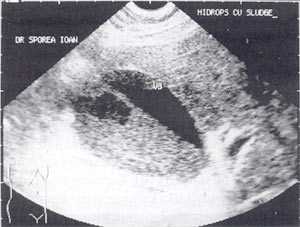

Кроме типичного вида, "желчный сладж" может иметь особый вид, похожий на круглое полипоидное объемное образование с острыми краями или неравномерным контуром ("опухолеподобный желчный сладж" или "сладжевые шарики" [12, 13]). При изменении положения больного видны перекатывающиеся или разрушающиеся шарики сладжа, затем снова формирующие исходное объемное образование (рис. 2-8).

Рис. 2. Желчный пузырь, наполовину заполненный сладжем.

Рис. 3. Большой желчный пузырь со сладжем.

Рис. 4. "Желчный сладж" у больного с циррозом печени.

Рис. 5. Желчный пузырь, заполненный сладжем, у больного циррозом.